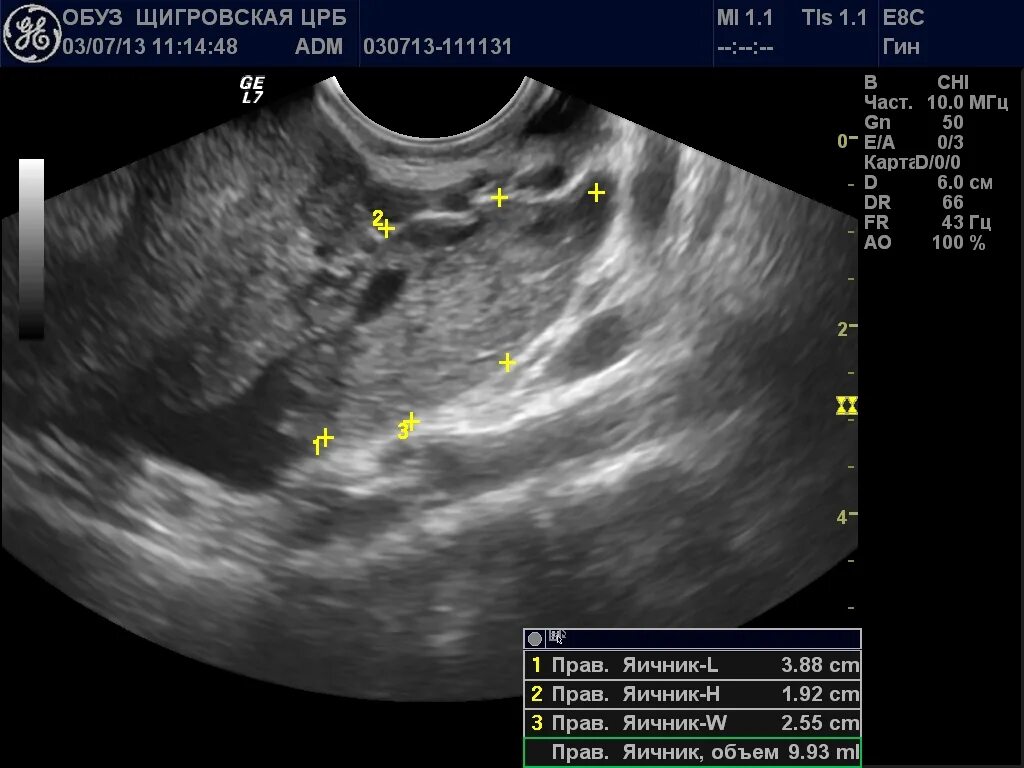

Параовариальная киста мкб